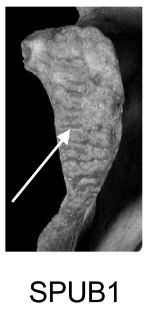

Demi-face antérieure (SPUB)

Changements morphologiques de la demi-face antérieure liés à la formation du rempart ventral.